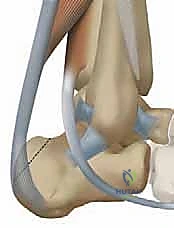

لفهم عبقرية هذه الجراحة، يجب أن نفهم التشريح. وتر العضلة المثنية الطويلة لإبهام القدم (Flexor Hallucis Longus - FHL) هو وتر يمر في الجزء الخلفي من الساق، قريباً جداً من وتر أخيل، ويمتد نزولاً ليتحكم في حركة انثناء إصبع القدم الكبير.

4. عزل وحصاد وتر FHL (Tendon Harvesting)

يتم تحديد مسار وتر FHL الذي يقع أعمق قليلاً من وتر أخيل. يتم فصل الوتر بعناية من نقطة اتصاله السفلية (عند منتصف القدم تقريباً) لضمان الحصول على طول كافٍ للنقل. وتجدر الإشارة هنا إلى أن قطع هذا الوتر لا يؤثر بشكل ملحوظ على وظيفة المشي أو حركة إصبع القدم الكبير، حيث تتولى عضلات أخرى هذه المهمة بكفاءة.

5. نقل وتثبيت الوتر (Tenodesis & Fixation)

هنا يتجلى الفن الجراحي. يتم حفر نفق صغير جداً في عظم الكعب (Calcaneus). يُسحب وتر FHL القوي ويُزرع داخل هذا النفق العظمي. يتم تثبيته باستخدام مسمار تداخلي حيوي (Bio-interference screw) يندمج مع العظم بمرور الوقت، مما يوفر تثبيتاً صخرياً قوياً.